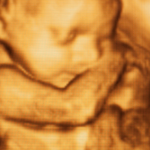

Échographies 4D

Des images précises et détaillées pour un suivi optimal de la grossesse.

Puis-je obtenir des photos de mon bébé à l’échographie ?

Oui, nous proposons un album photo personnalisé pour les futures mamans, incluant des images capturées lors des échographies.